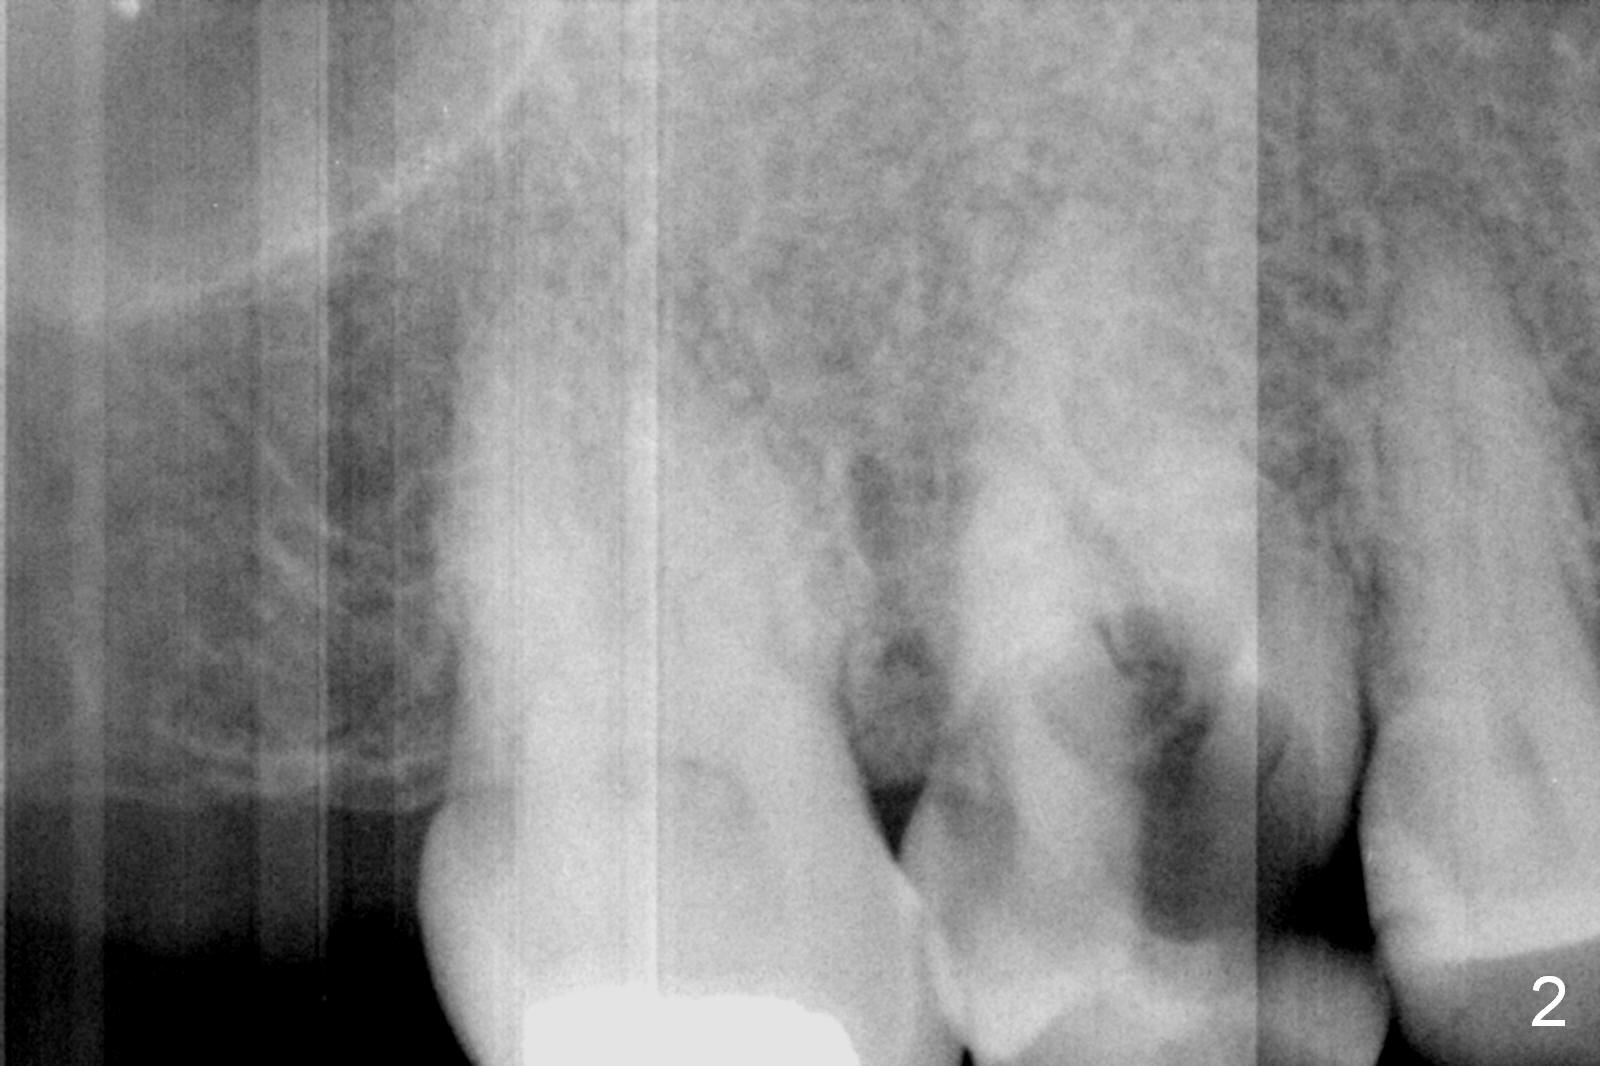

A 52-year-old woman is a dental phobic. Her main concern is the tooth #3 with caries apparently involving the furca (Fig.1 ^). Before extraction, take photos to show a polyp in the pulpal chamber, which is most likely periodontal. After extraction (prepare surgical handpiece, since the tooth most likely fractures at extraction), take photos to show furcal perforation, while the socket is packed with 3 pieces of gauze soaked with Metronidazole. There is apparently sufficient bone apical to the roots (Fig.2). To achieve primary stability, use an implant as long as possible (13 mm of IBS, Fig.3 (implant is drawn to be placed too superficial)) with large diameter appropriate to the septum. The plateau of the implant will be placed apical to the crests and coronal to the septum.